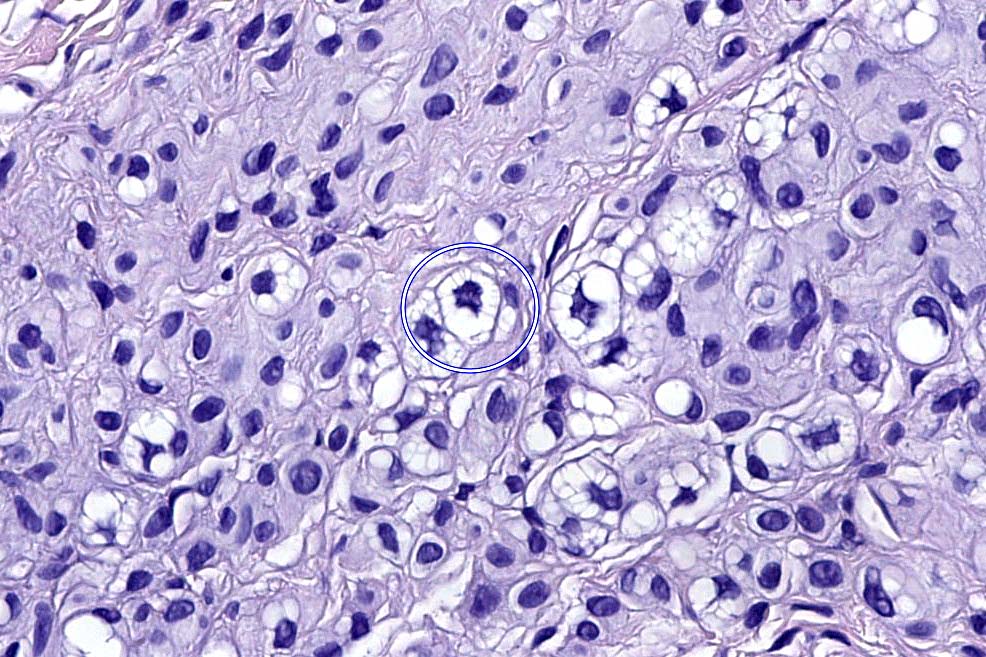

.Balloon cell nevs genrally has uniform, hyperchromatic nuceli (as opposed to the vesicular nuclei with prominent nucleoli) seen in melanoma. Mitoses are absent.(In my experience, balloon cell melanoma is more common than balloon cell nevus).

. In some balloon cell nevi, the microvesicles may result in nuclear scalloping reminiscent of a sebaceous tumor. In cases where there is real doubt, immunohistochemistry (S100), SOX10) will resolve the problem.

The importance of the entity is that it must always be distinguished from balloon cell melanoma. All cases should be scrutinized very carefully for pleomorphism and mitotic activiy before rendering a diagnosis of balloon cell nevus.